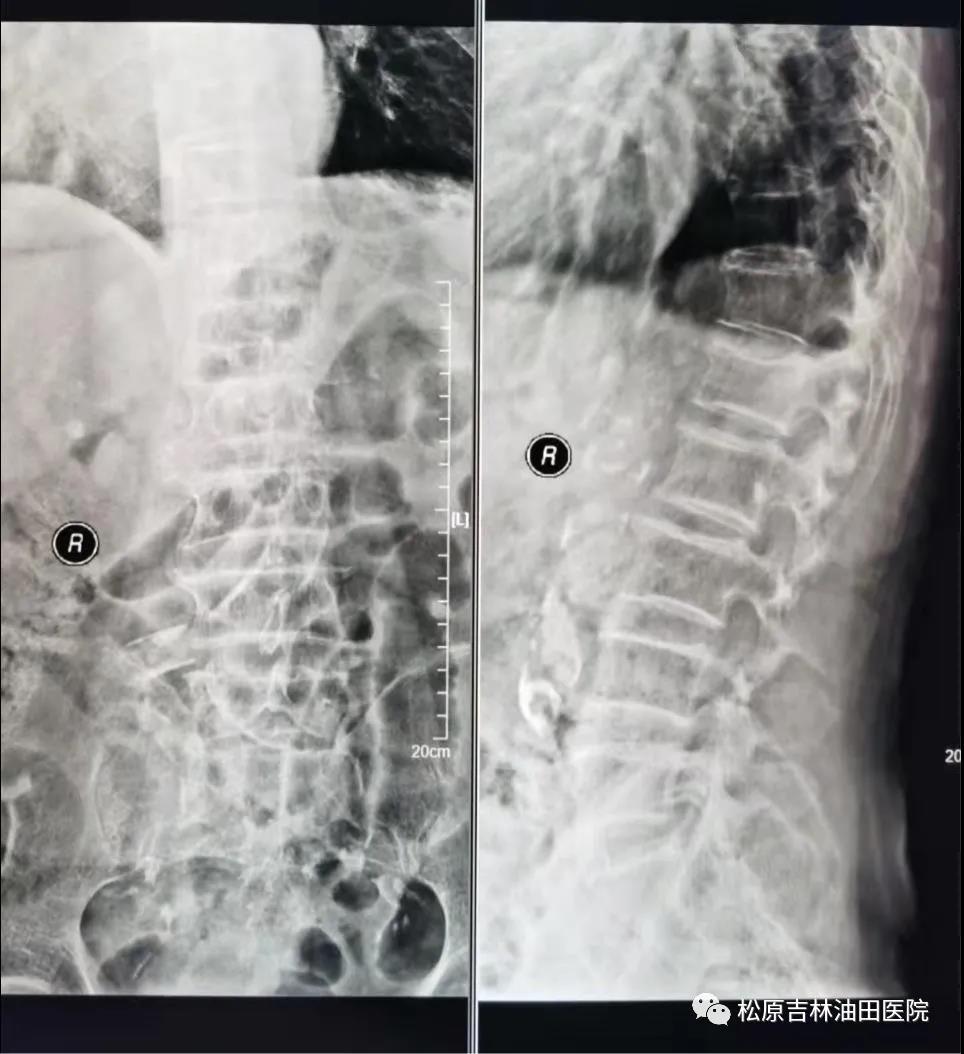

患者**苹 术后影像(骨水泥得到良好弥散、填充、支撑)与术前影像对比